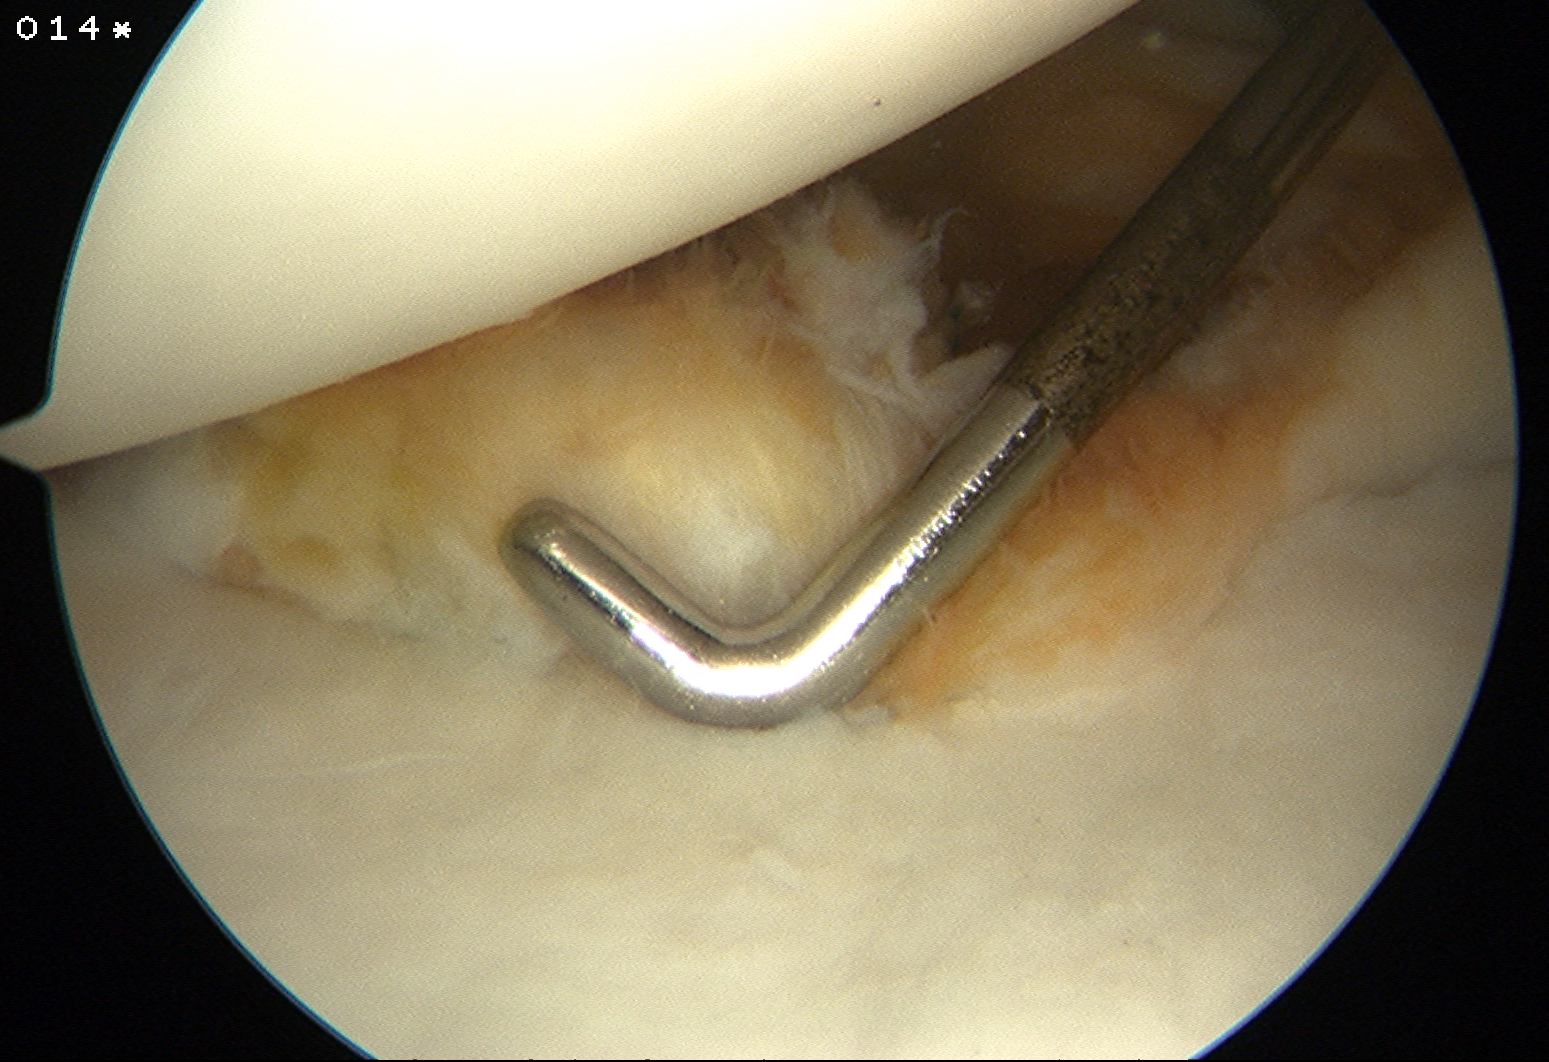

Mobilize labrum

Shoulder Scope Bankart RaspShoulder Stabilisation Labral Mobilisation

Labral mobiliser / rasp

- labral tear can be obvious, but may have partially healed or healed medially

- change camera to anterosuperior portal for better view

- mobilize until can see subscapularis muscle underneath

- need to be able to advance labrum medially and superiorly for repair